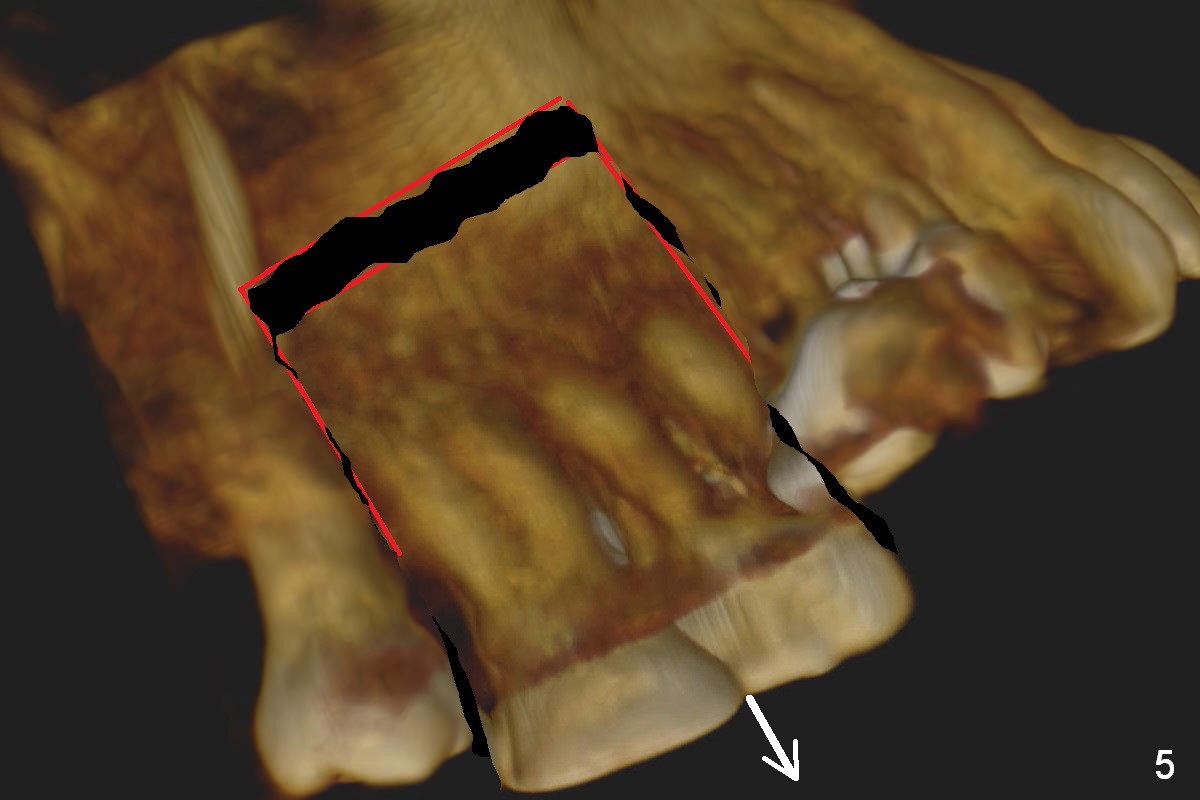

Orthodontic intrusion with mini-implants does not seem to work. When segmental brackets and bands are supplemented, the neighboring tooth (#14) becomes loose. CBCT 3 D and sagittal section show ~3 mm supraeruption of the teeth #2 and 3 (Fig.1,2). Diagnostic wax up demonstrates that the teeth #2 and 3 need to be intruded for 4 and 2 mm, respectively. Buccal gingival sulcus and anterior oblique incisions are shown in Fig.3 (red line). Osteotomy will be made with surgical fissure bur and chisels (Fig.4 red lines). The segment is down fractured (Fig.5 arrow). Apical bone is removed with acrylic bur and/surgical burs (Fig.6 cross lines). The segment is elevated and checked with a prefabricated splint out of diagnostic wax up. Insert a thicker orthodontic wire into brackets and bands buccally.